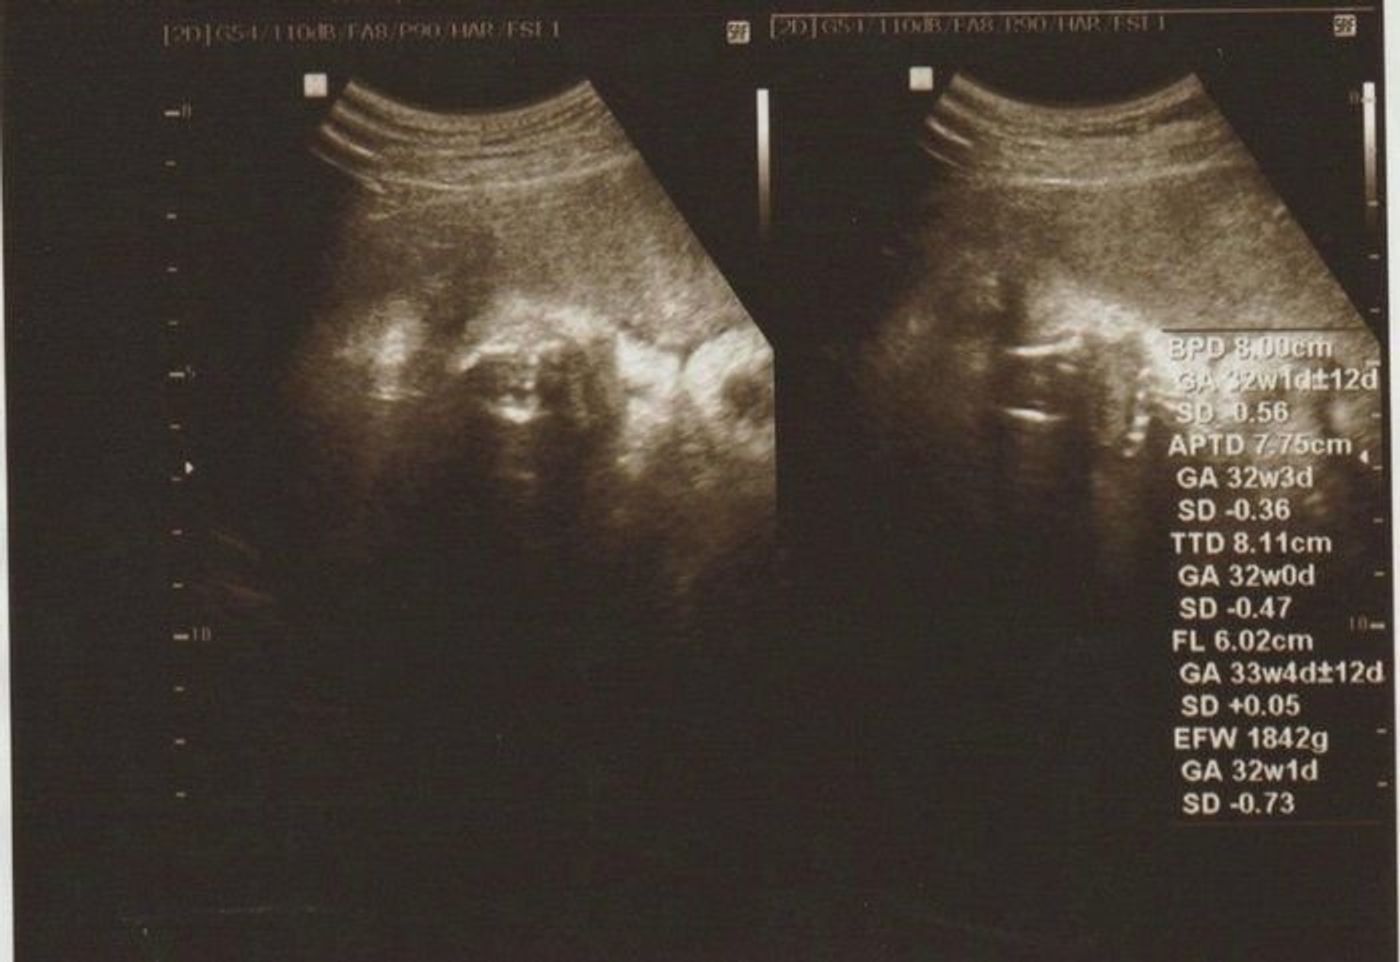

妊娠33週目の胎児(赤ちゃん)の大きさ 前回の記事でも書いたんですが、妊娠33週6日目のエコー検査で、私のお腹の中の赤ちゃんは推定体重2112gになっていました。 ついに00gオーバーです! ! 妊娠33週目で、胎児(赤ちゃん)の 身長は45cm前後になり妊娠30週以降だと1時間以内に5回以上の張り このぐらい頻繁にお腹の張りを感じたときは、お腹の張りの間隔を測ってみてください。 お腹の張りの間隔が 規則的 で、 張る間隔が短く なってきているときは、流産や早産の危険性がありますので、産婦人科を